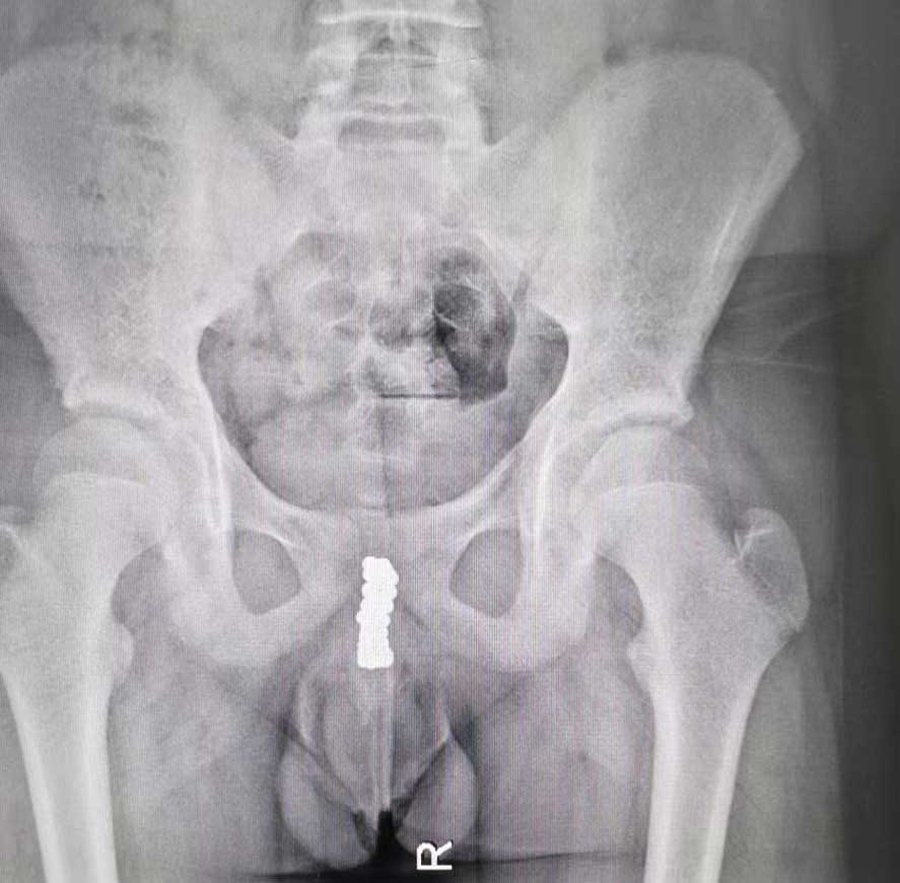

“孩子说把磁力珠塞进尿道里了。”家长一句话让在场人大吃一惊。果然,医生查体时,在小宇会阴区域摸到了珠子。CT检查同样证实尿道内有珠子样的异物,并且吸附在一起。在医生的追问下,小宇才满眼含泪地说了实话。原来,出于好奇,他趁家长不注意,将磁力珠一颗一颗塞进尿道口,并没告诉家长,等出现排尿疼痛、血尿后,才不得不跟家长说起。由于磁力珠位于后尿道膜部位置,所以医生从后尿道位置剖开,手术取出10余颗磁力珠。术中,C型臂透视显示,膀胱内还有一团磁力珠,医生通过下腹部耻骨联合上的切口,将膀胱打开,又取出30多颗磁力珠。手术前后近3个小时,共取出近50颗磁力珠。由于磁力珠在尿道及膀胱内的长时间吸附,取出时附着着脓性分泌物,说明尿道内已经感染了。